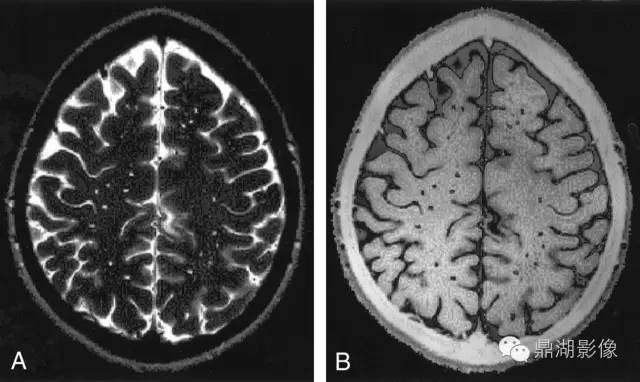

周围血管间隙(PVS)

PVS 的同义词包括 Virchow–Robin 间隙和 3型腔隙或筛(位于基底节区时),这些名词术语均被用于描述可见的 PVS。2012 年的共识指南将 PVS 定义为当穿过灰质或白质时,其走向与常见血管走向一致的充满液体的间隙。在所有影像序列中,这些间隙与脑脊液的信号强度相同,在与血管走向平行的层面上呈线性,在与血管走向垂直的层面上呈圆形或卵圆形,直径约< 3 mm ;通常在基底节下部很明显,可见其向心穿过半球白质进入中脑,但是在小脑中较少见。这些间隙可以表现出局部的扩大,有时甚至可以扩大至直径为 10 ~ 20 mm,甚至表现出聚集效应。PVS 必须与假定血管源性的腔隙灶进行鉴别。与假定血管源性的腔隙灶相比,病理状态下 PVS 的直径通常≤ 3 mm,并且在 T2 加权图像或 FLAIR 序列图像上不表现为围绕着充满液体的间隙的高信号圈,除非间隙跨越了白质高信号区。

PVS

4.2.4 PVS

指南对PVS的定义为:穿过灰质或白质,与常见血管走行一致的充满液体的间隙。PVS扩张在MRI上主要表现为直径<3 mm的圆形、卵圆形或线形的,T1WI上低信号、T2WI上高信号(与脑脊液信号强度一致)、FLAIR上低信号、DWI上无弥散受限的病灶,通常边界清晰、无对比剂增强效应和占位效应。病灶形状取决于成像平面,成像平面与血管走行平行时呈线性,与血管走行垂直时呈圆形或卵圆形。该征象多见于基底节区靠近前联合附近、脑凸面皮层下、半卵圆中心、脑干及外囊,很少出现在小脑,常与假定血管源性的腔隙灶同时出现,需加以鉴别。普遍接受的用来区分两者的特点是PVS直径一般不超过3 mm,且在T2WI和FLAIR上不表现为围绕脑脊液样信号的环状高信号,除非间隙跨越白质高信号区。